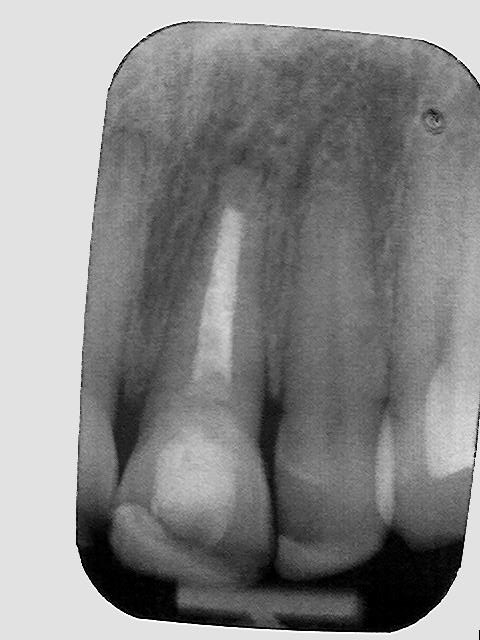

Upper Incisor trauma case primary root canal treatment and rebuild